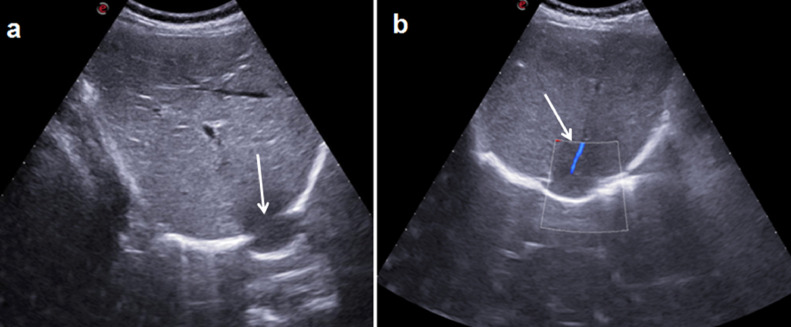

Fig.2 – US.

a: B-Mode US scans show hepatic parenchyma herniation (long arrow) across a continuum of diaphragm (arrow). b: Color Doppler US shows a hepatic vessel (arrow) in continuity with herniated parenchyma.